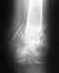

Добрый день! Моей бабушке 86 лет, 2 недели назад упала, сегодня получили снимок и заключение: чрезвертельный перелом правого бедра со смещением. Нужна ли операция? Можно ли сделать ее у вас? Сколько будет стоить? Могу выслать снимок. Спасибо.

• Кликните для загрузки файла снимок 008.jpg

Операция нужна, чем раньше - тем лучше. Пока пациентке надо начать вводить антикоагулянты (клексан, фраксипарин). Можно сделать у нас. Звоните 371-31-82 или заедьте к нам на Московскую, 12 за вызовом на госпитализацию.